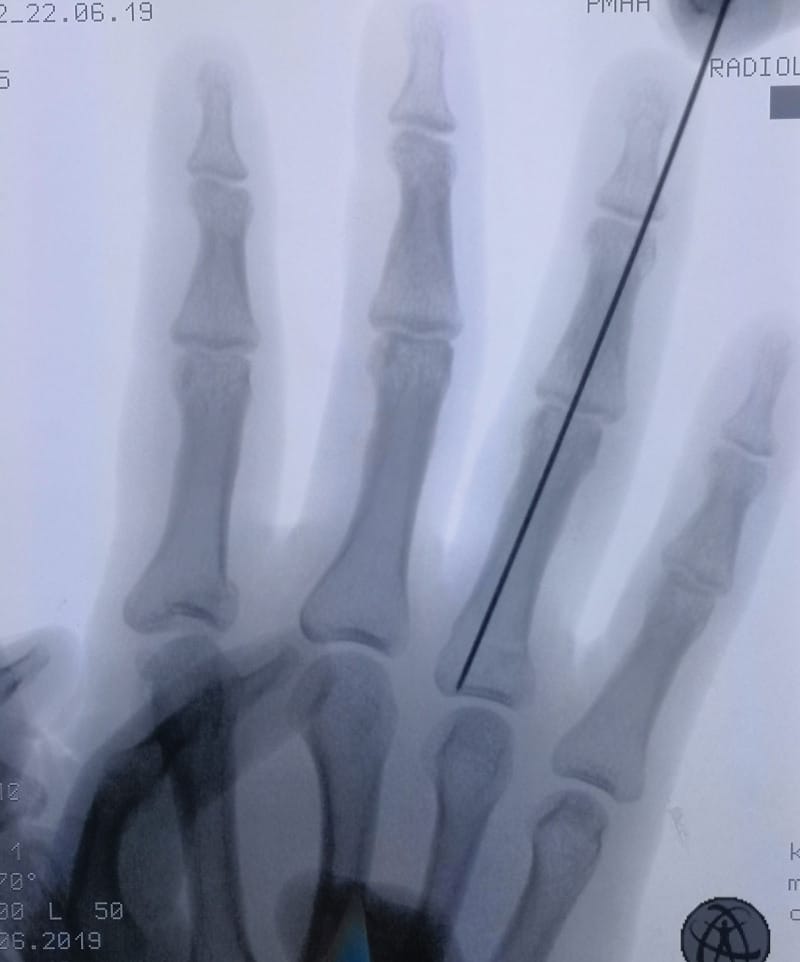

Seymour Fracture Anatomy X-Ray

This week’s image features a classic Seymour fracture. It typically presents with a nailbed injury and flexed DIP joint, with the fracture line extending through the physis.

Image 1: Clinical image showing nail avulsion and volar displacement.

Image 2: X-ray confirming displaced juxta-epiphyseal fracture.

Note: Seymour fractures are open fractures until proven otherwise. Urgent washout, reduction, and antibiotics are essential.